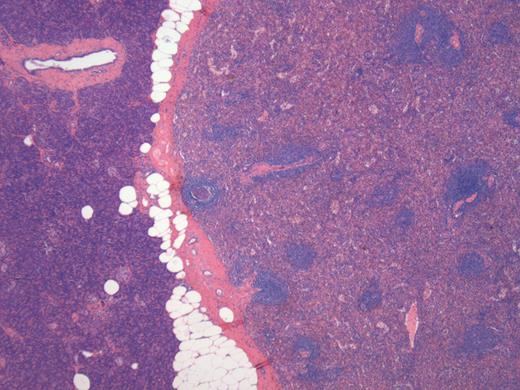

A 76-year-old male presented to his general practitioner with nausea, weight loss and change in bowel habit. A recent colonoscopy was unremarkable, a computed tomography (CT) abdomen and pelvis showed a homogenously enhancing 13-mm lesion in the tail of the pancreas, with the reported differentials including neuroendocrine tumour or a pancreatic adenocarcinoma. A subsequent magnetic resonance imaging (MRI) illustrated the lesion enhancing homogenously in the portal venous post-contrast phase suggesting a solid neoplastic lesion, likely to be primary (Fig. 1). He went on to have a distal pancreatectomy and splenectomy with an uneventful recovery. Pathology revealed a splenunculus with no evidence of malignancy (Fig. 2).

Histology of the lesion showing the normal pancreas on the left with the accessory spleen on the right